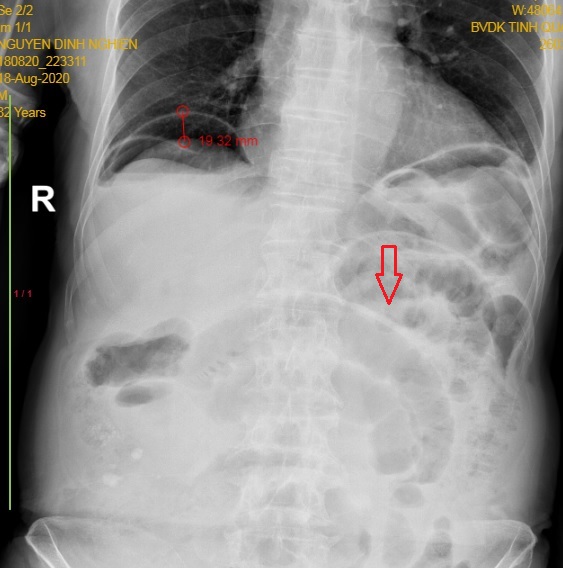

Hình 1: Phim bụng chụp vào ngày hậu phẫu thứ 8 mổ cắt ruột thừa nội soi với hình ảnh liệt ruột (mũi tên đỏ) và liềm hơi dưới cơ hoành P cao 19,32mm - Bệnh nhân được chẩn đoán bục gốc ruột thừa.

Tác giả nhận thấy có sự khác biệt về chiều cao ban đầu của liềm hơi dưới cơ hoành giữa 2 nhóm (nhóm rò miệng nối có chiều cao ban đầu của liềm hơi dưới cơ hoành lớn hơn, p=0,04). Còn về tiến triển thì liềm hơi dưới cơ hoành ngày càng giảm độ cao ở nhóm khí sinh lý, trong khi nhóm rò miệng nối ngày càng tăng độ cao. Bằng cách vẽ đường cong ROC của chiều cao ban đầu của liềm hơi dưới cơ hoành, diện tích dưới đường cong tính được là 0,69. Tác giả đã tìm được điểm cắt 11,7mm (chiều cao ban đầu của liềm hơi dưới cơ hoành) là điểm phân biệt liềm hơi sinh lý hay rò miệng nối. Hình ảnh liệt ruột sau mổ cũng cao hơn có ý nghĩa ở nhóm rò miệng nối (P 0.01). Như vậy có 3 đặc điểm trên X quang bụng giúp chúng ta nghĩ đến thủng tạng rỗng sau mổ đó là: chiều cao của liềm hơi dưới cơ hoành ban đầu, tiến triển của chiều cao này và hình ảnh liệt ruột.

- Chiều cao ban đầu của liềm hơi dưới cơ hoành là một dấu hiệu có giá trị với điểm cắt 11.7 mm để phân biệt liềm hơi sinh lý hay rò miệng nối. Kết quả này tương đối phù hợp với nghiên cứu của Millitz K.(1994) về chiều cao của liềm hơi sinh lý[6]. Millitz K.(1994) nhận thấy tại mọi thời điểm chiều cao này đều nhỏ hơn 10 mm. Tuy nhiên trong nghiên cứu của Lee C.H.(2012) diện tích dưới đường cong tính được chỉ là 0,69 nên kết quả này chỉ có tính tham khảo cần được đánh giá thêm với các nghiên cứu có cỡ mẫu lớn hơn. Theo kinh nghiệm của chúng tôi xì rò thường xảy ra vào ngày thứ 5 sau mổ. Tại thời điểm này hơi tự do thường đã hấp thu hết hay chỉ tồn tại dưới dạng vết. Nếu có liềm hơi và chiều cao đo được trên 11.7 mm thì cần cảnh giác có xì rò. Kết hợp với các triệu chứng lâm sàng và cận lâm sàng khác để có quyết định mổ lại sớm cho bệnh nhân

Một liềm hơi lớn (chiều cao  >11,7 mm) cùng với hình ảnh liệt ruột vào thời điểm khí sinh lý sau mổ hầu hết đã được hấp thu  (từ ngày hậu phẫu thứ 5) là những đặc điểm trên xquang bụng đứng nghi ngờ tổn thương tạng rỗng sau mổ.